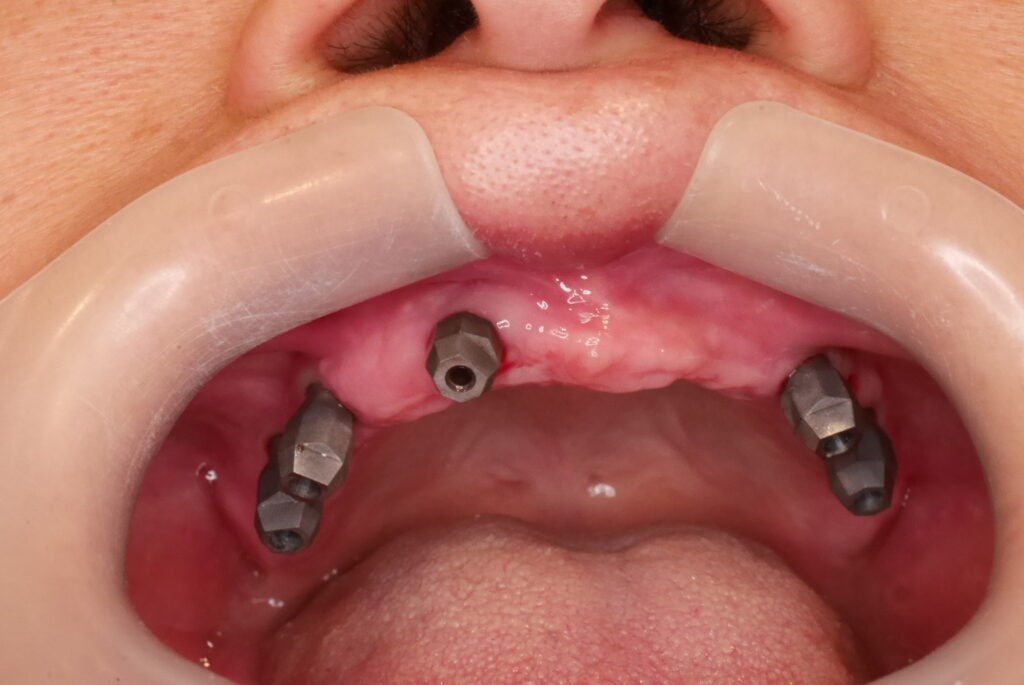

殘根拔除後,植入6支人工牙根

數位取模,置入植體掃描桿

數位取模 德國口掃機 口內精準掃描